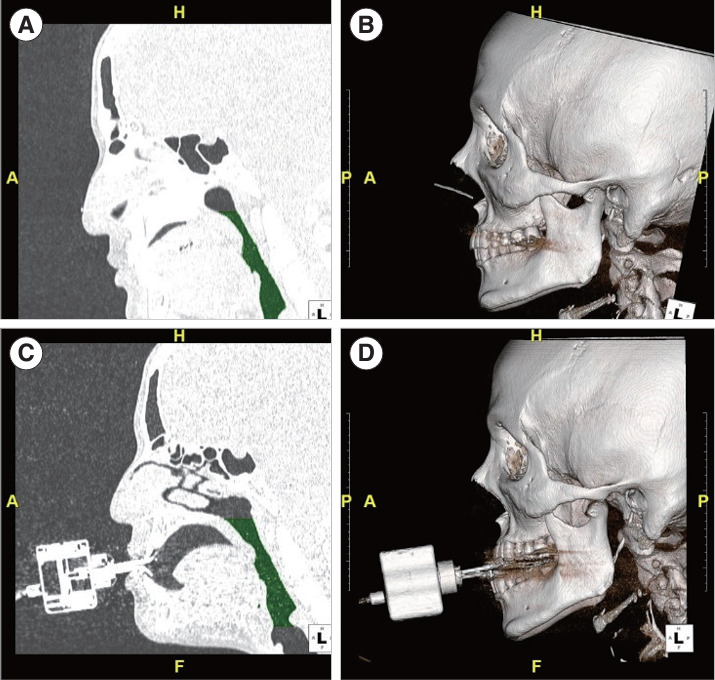

Objectives: Although mandibular advancement device (MAD) treatment is effective for obstructive sleep apnea (OSA), some concerns remain regarding its potential therapeutic impact and side effects. Thus, we developed a novel MAD that auto-titrates depending on its position in patients with OSA. We conducted a clinical trial to determine the efficacy of an auto-titrating mandibular advancement device (AMAD) for treating OSA.

Methods: Fourteen patients diagnosed with OSA participated in this study. Polysomnography (PSG) was performed at the beginning of the clinical trial, and after 3 months of treatment, PSG with AMAD in situ was conducted.